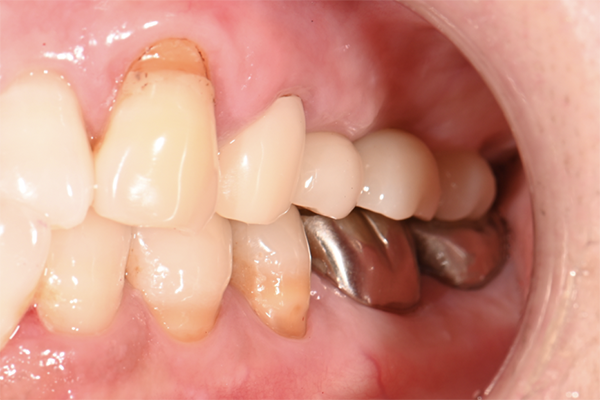

| 主訴 | 歯が痛い |

|---|---|

| 治療内容 | 右上奥歯に対するインプラント治療 (今後右下に対してもインプラント治療を予定) |

| 治療期間 | 6ヶ月 |

| 治療費 | 44万5千円 |

| 治療 リスク | インプラントを埋入したあと3ヶ月程度待ち時間が必要。 その期間は仮歯を使用していただきます。 |